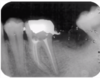

A = radiograph of mandibular with inadequate root filling and asymptomatic apical periodontitis.

B = the tooth has been retreated conservatively through the crown.

C = complete periapical repair is evident at the 6-month control.

A = radiograph of mandibular with inadequate root filling and asymptomatic apical periodontitis. B = the tooth has been retreated conservatively through the crown. C = complete periapical repair is evident at the 6-month control.